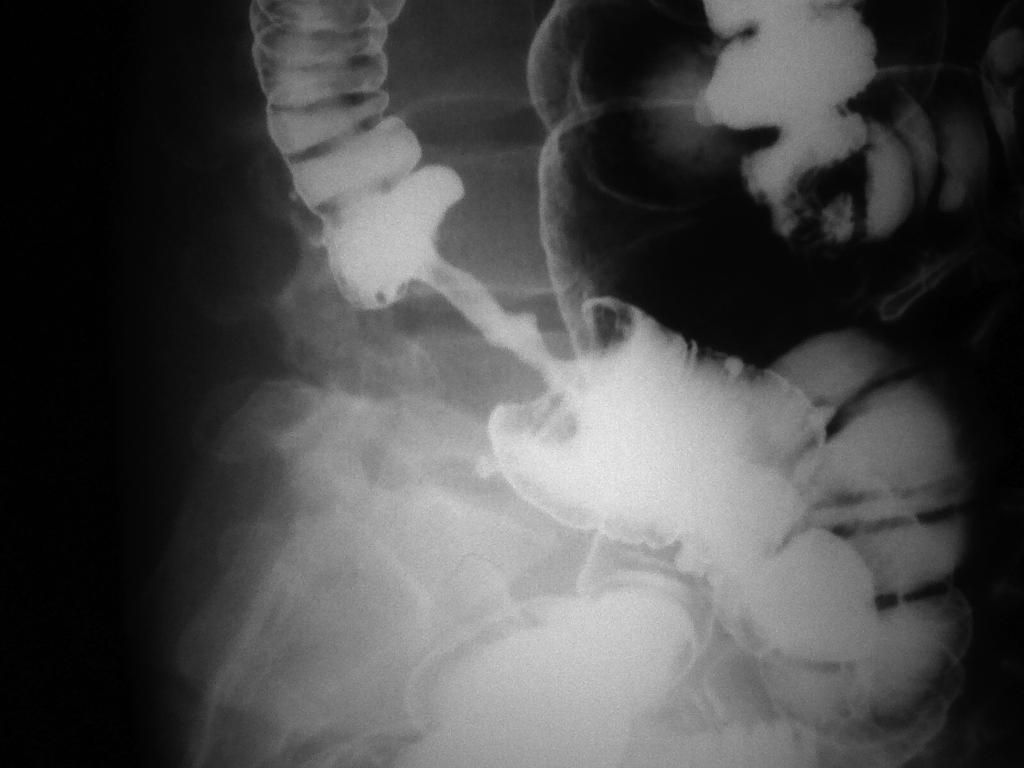

"Apple Core Sign" on X-ray in a patient with Colon Cancer

Cancer

Radiology

Carcinoma

Sign

X Ray